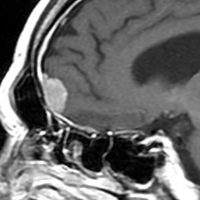

典型的な髄膜腫

この髄膜腫は中程度の大きさのものです。円蓋部髄膜種という最も多い最も手術の簡単なタイプです。麻痺や失語症やてんかんなどの症状はありません。とても美しくて若い女性の髄膜腫でしたが,子供に遺伝はしませんし,癌などと違ってタバコなどこれといった原因がなくて発生するものです。

MRIでの髄膜腫の見え方は撮影の仕方によっていろいろです。左からT1強調画像,T2強調画像,フレア画像といいます。腫瘍の横に小さく白い領域がありますが,これは脳の腫れた部分で脳浮腫といいます。髄膜腫があると周囲に脳浮腫が生じることがあります。

最も見やすいのが,ガドリニウム造影剤を注射して撮影するものです。一般的に髄膜腫は造影剤で白く映し出されます。この腫瘍は左脳側にあります。MRIの軸面という輪切りの写真では左右が逆になりますから注意してください。脳を下から見た図になっています。MRIはいろいろな方向から腫瘍を見ることができますが,右は冠状断という正面から見た図です。よく見ると腫瘍の上と下のはじっこに線状に糸を引いたように造影される部分があります。これをテールサイン(しっぽのサイン)といいます。腫瘍が硬膜に沿って延びている可能性があることを示しています。